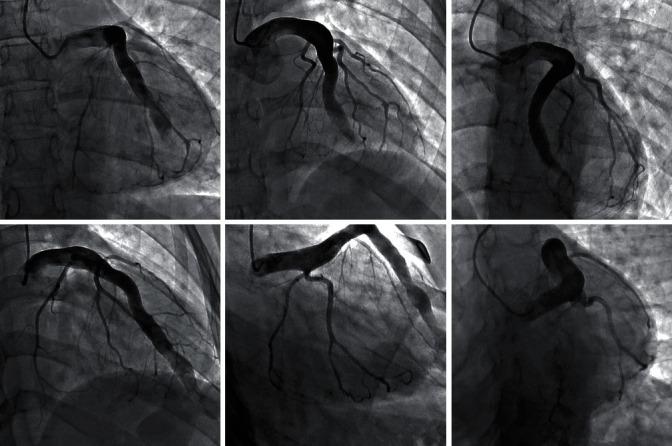

A 27-year-old female presented to our emergency department in ventricular tachycardia. During her workup, she was found to have an extremely rare giant aneurysmal left anterior descending artery (LAD) ending in a coronary fistula to the right ventricle (RV). After stabilization, a variety of treatment options were considered, as there is no standard first-line treatment.

一名27岁女性因室性心动过速被送至我院急诊科。在检查过程中,发现她患有极为罕见的巨大动脉瘤样左前降支动脉(LAD),其末端形成冠状动脉瘘并通向右心室(RV)。病情稳定后,由于没有标准的一线治疗方法,故考虑了多种治疗方案。